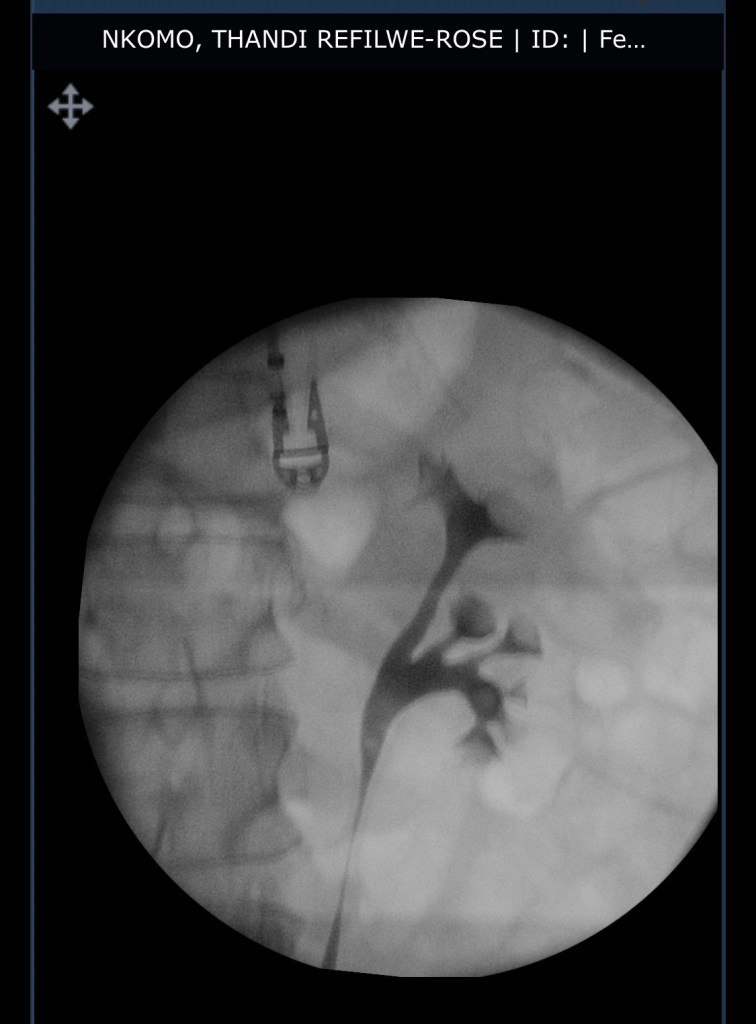

I am struggling scarily now. As predicted, the stricture (narrowing) has returned to my urethra. I spend so long trying to PUSH urine out that my feet both become numb and the pain when I have to get up and use them is horrendous. I almost cried out to my family to try rub some life into my feet earlier on today. It’s so bad, the struggle, how long it takes me to get just a few drops out, that the other night I suddenly heard my husband shout, “Are you dead?”

I feel like my body is conspiring against me. And my questions about the urethra is- WHY? What’s causing this? And what will the long term plan be? I can’t keep having procedures under anesthesia every two months. I had the surgery on November 15. Symptoms began in December.

And here I sit, scared. This will set my kidneys backwards. What if I end up totally unable to urinate before Feb 19’s appointment that will only set up a date for the actual procedure to help me? I’m terrified of self catheterisation.